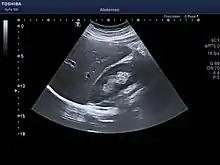

The diagnosis of liver disease is made by liver function tests, groups of blood tests, that can readily show the extent of liver damage. If infection is suspected, then other serological tests will be carried out. A physical examination of the liver can only reveal its size and any tenderness, and some form of imaging such as an ultrasound or CT scan may also be needed.

Sometimes a liver biopsy will be necessary, and a tissue sample is taken through a needle inserted into the skin just below the rib cage. This procedure may be helped by a sonographer providing ultrasound guidance to an interventional radiologist.[65]